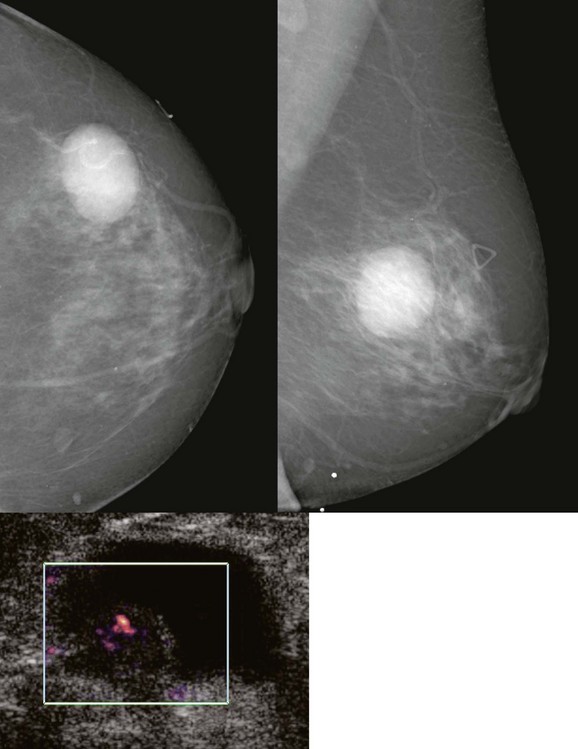

FIGURE 11-6 Medullary Carcinoma.

This 44-year-old woman presented with a palpable mass (triangle) that corresponds to an oval, relatively circumscribed, high-density mass. US demonstrates a hypoechoic, solid, oval mass with posterior acoustic shadowing.

On mammography, medullary carcinoma typically presents as a round or oval, circumscribed mass without calcifications. It is often palpable.